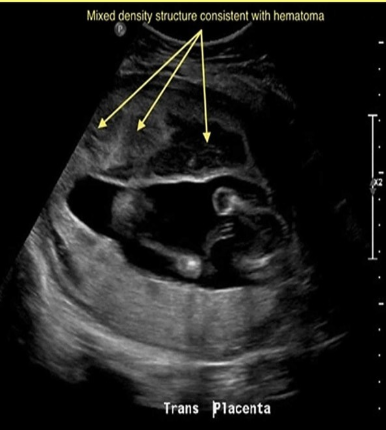

Maternal cocaine abuse is assoc w/what critical findings on fetal US

.

a) fetal CHF

b) placental abruption + premature birth

c) fetal hydrops + demise

d) theca lutein cyst formation